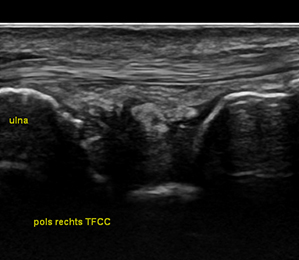

Orthopedische echografie, een blessure nader bekeken .........